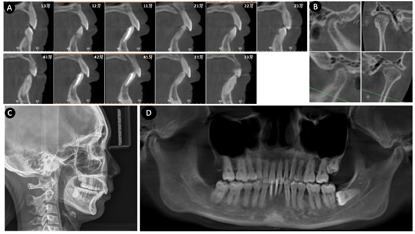

治疗后的CBCT影像分析显示上下前牙牙根均纳入牙槽骨中央位置。骨开窗的程度得到一定的改善,CBCT拟合的全景片显示,较首诊时相比,牙槽骨高度未见进一步下降,多数牙牙槽嵴顶附近出现明显的骨白线,36牙近中角型骨吸收消失——所有这些表征说明骨吸收转为静止状态。髁状突与关节窝的关系未发生明显改变。头颅侧位片及X线头影测量分析对比显示下颌平面顺时针旋转,上下前牙唇倾的同时均有显著的压低,下后牙有一定程度的伸长。其中FH-MP角27.9°,OP-FH角14.4°,U1-L1角127.2°,U1-SN角89.4°,L1-MP角109.3°,U1-PP距29.8 mm,U6-PP距21.4 mm, L1-MP距40.6 mm,L6-MP距32.9 mm。(治疗的影像资料详见图7,头影测量的前后对比详见图8)。

随访:患者矫治一年后随访正畸效果及牙周状况均较稳定(图9)。